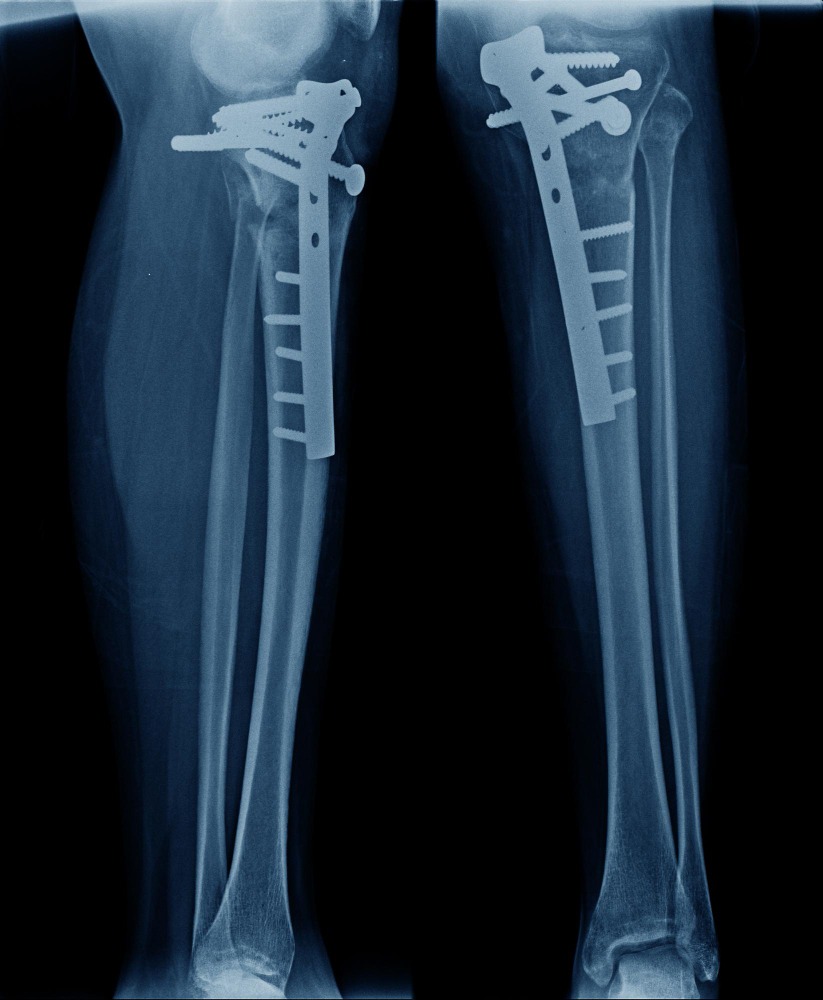

Complex Trauma Surgery Treatment in Moshi – Specialized Orthopedic Care for Severe Injuries